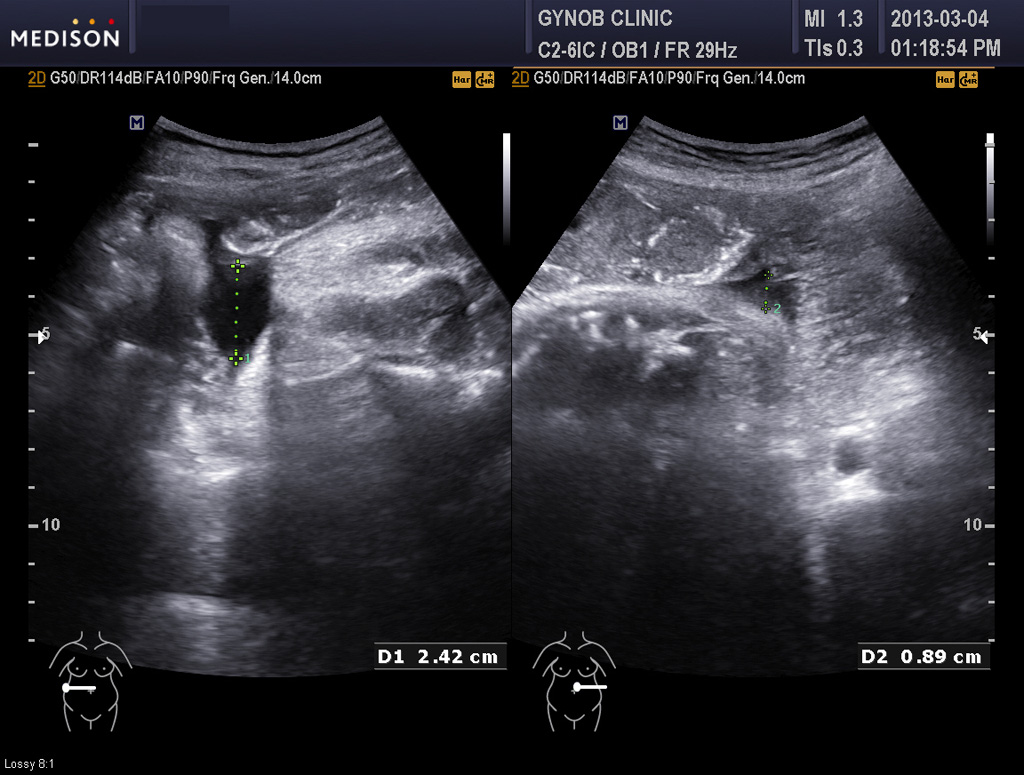

그런데 그 산모는 초음파 검사상 태아의 방광이 수시간 동안이나 비워지지 않고 꽉 찬 상태로 보여 혹시 태아의 비뇨기 계통의 기형인 "요관 말단 판막 (posterior urethral valve)"이라고 하는 기형이 있지 않은가 하는 의심이 들었습니다.

요관 말단 판막은 그리 흔한 기형은 아니지만 남자 아기에게서 주로 생기고 방광의 소변이 원활하게 체외로 나오지 못하는 기형입니다.

따라서 그런 기형이 있을 경우 방광은 많이 커지고 양수는 줄어들게 됩니다.

콩팥도 영향을 받는 경우가 많은데 그 산모의 태아는 콩팥은 이상이 없어 보였지만 경미한 타입의 판막증에서는 그럴 수도 있기 때문에 태아의 건강을 생각하여 산모와 상의하여 대학 병원에서 출산하기로 결정을 하였습니다.

아래 사진은 그 산모분의 산전 진찰시 초음파 사진인데 위는 양소 과소증을 나타내 주는 사진이고 아래는 태아 방광의 사진입니다.